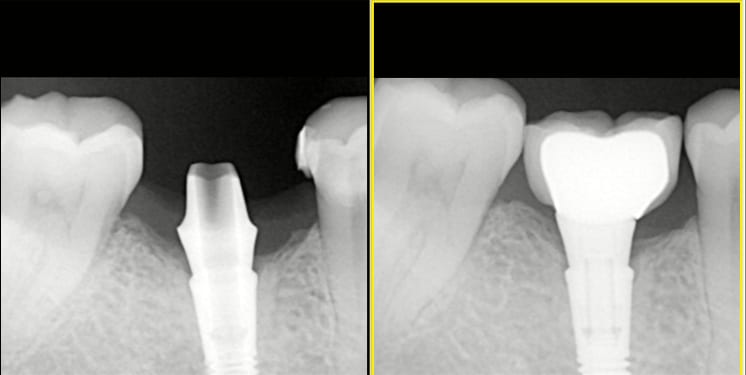

je dois sortir le pilier d'un implant Astratech osseospeed TX en 46.

La patiente a une prothèse scellée qui se descelle sans arrêt car peu de hauteur , même avec un ciment définitiif .

je pense faire une couronne transvissée pour résoudre le problème .

Si je ne me trompe, la connexion est un cône morse et j'ai lu quelque-part qu'il pouvait être nécessaire d'utiliser un instrument extracteur pour séparer le pilier de l'implant, pour certaines marques .

Connexion à 12 degrés sur Astra. Ce n’es Pas un cône morse. Pas besoin d’instr De dépose. Une pince gouge suffit.

Torque à 20N jusqu’à 4mm (océan)

Torque à 25 N pour les diamètres 4,5 et 5mm(Lilas).